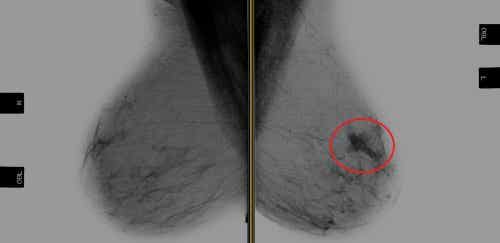

Rak piersi HER-2 dodatni oznacza, że występuje neoplazja oraz nadmiar receptorów białka HER-2. Białka HER-2 to receptory komórek piersi produkowanych przez gen HER-2, które są potrzebne do funkcjonowania i regeneracji piersi.

Rak piersi HER-2 dodatni stanowi 20 do 30% przypadków nowotworów piersi. Ten typ raka ma kiepskie rokowania, gdyż ma tendencję do nawracania.